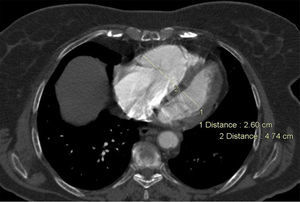

Para além da avaliação da carga embólica na TCMD, foram efetuadas medições quantitativas dos diâmetros das estruturas vasculares (VCS e VA) e cardíacas (VD, VE, ratio VD/VE; SC, AP, Ao, ratio Ap/Ao) relacionadas com a árvore pulmonar. O desvio do SIV e o refluxo de contraste na veia cava inferior (VCI) foram avaliados qualitativamente, de forma a definir os sinais de DVD (Figuras 2-5).

Na angio-TC, o grupo B apresentou diâmetros do VD, ratio VD/VE (p-0,002), VCS, VA e SC superiores. Os diâmetros da AP e o ratio AP/aorta foram semelhantes.

A percentagem de sobrecarga no septo IV e refluxo na VC inferior (p-0,001) foram superiores no GB, revelando-se o QS > 18 pontos, preditor independente de DVD (VD/VE > 1) (OR:10,85 [CI 3,20-36,77]; p<0,001) (AUC ROC: 0,79; p<0,001) com uma sensibilidade estimada em 78,4% e especificidade em 79% (Figura 1, Tabela 7).

Na angio-TC, o QS correlacionou-se linearmente com os parâmetros de DVD avaliados (diâmetros do VD, VCS, VA e SC; ratio VD/VE e AP/Ao; percentagem de sobrecarga no SIV e de refluxo na VCI), conferindo à carga embólica avaliada por QS um potencial multiparâmetros que ainda não se encontrava descrito na literatura.